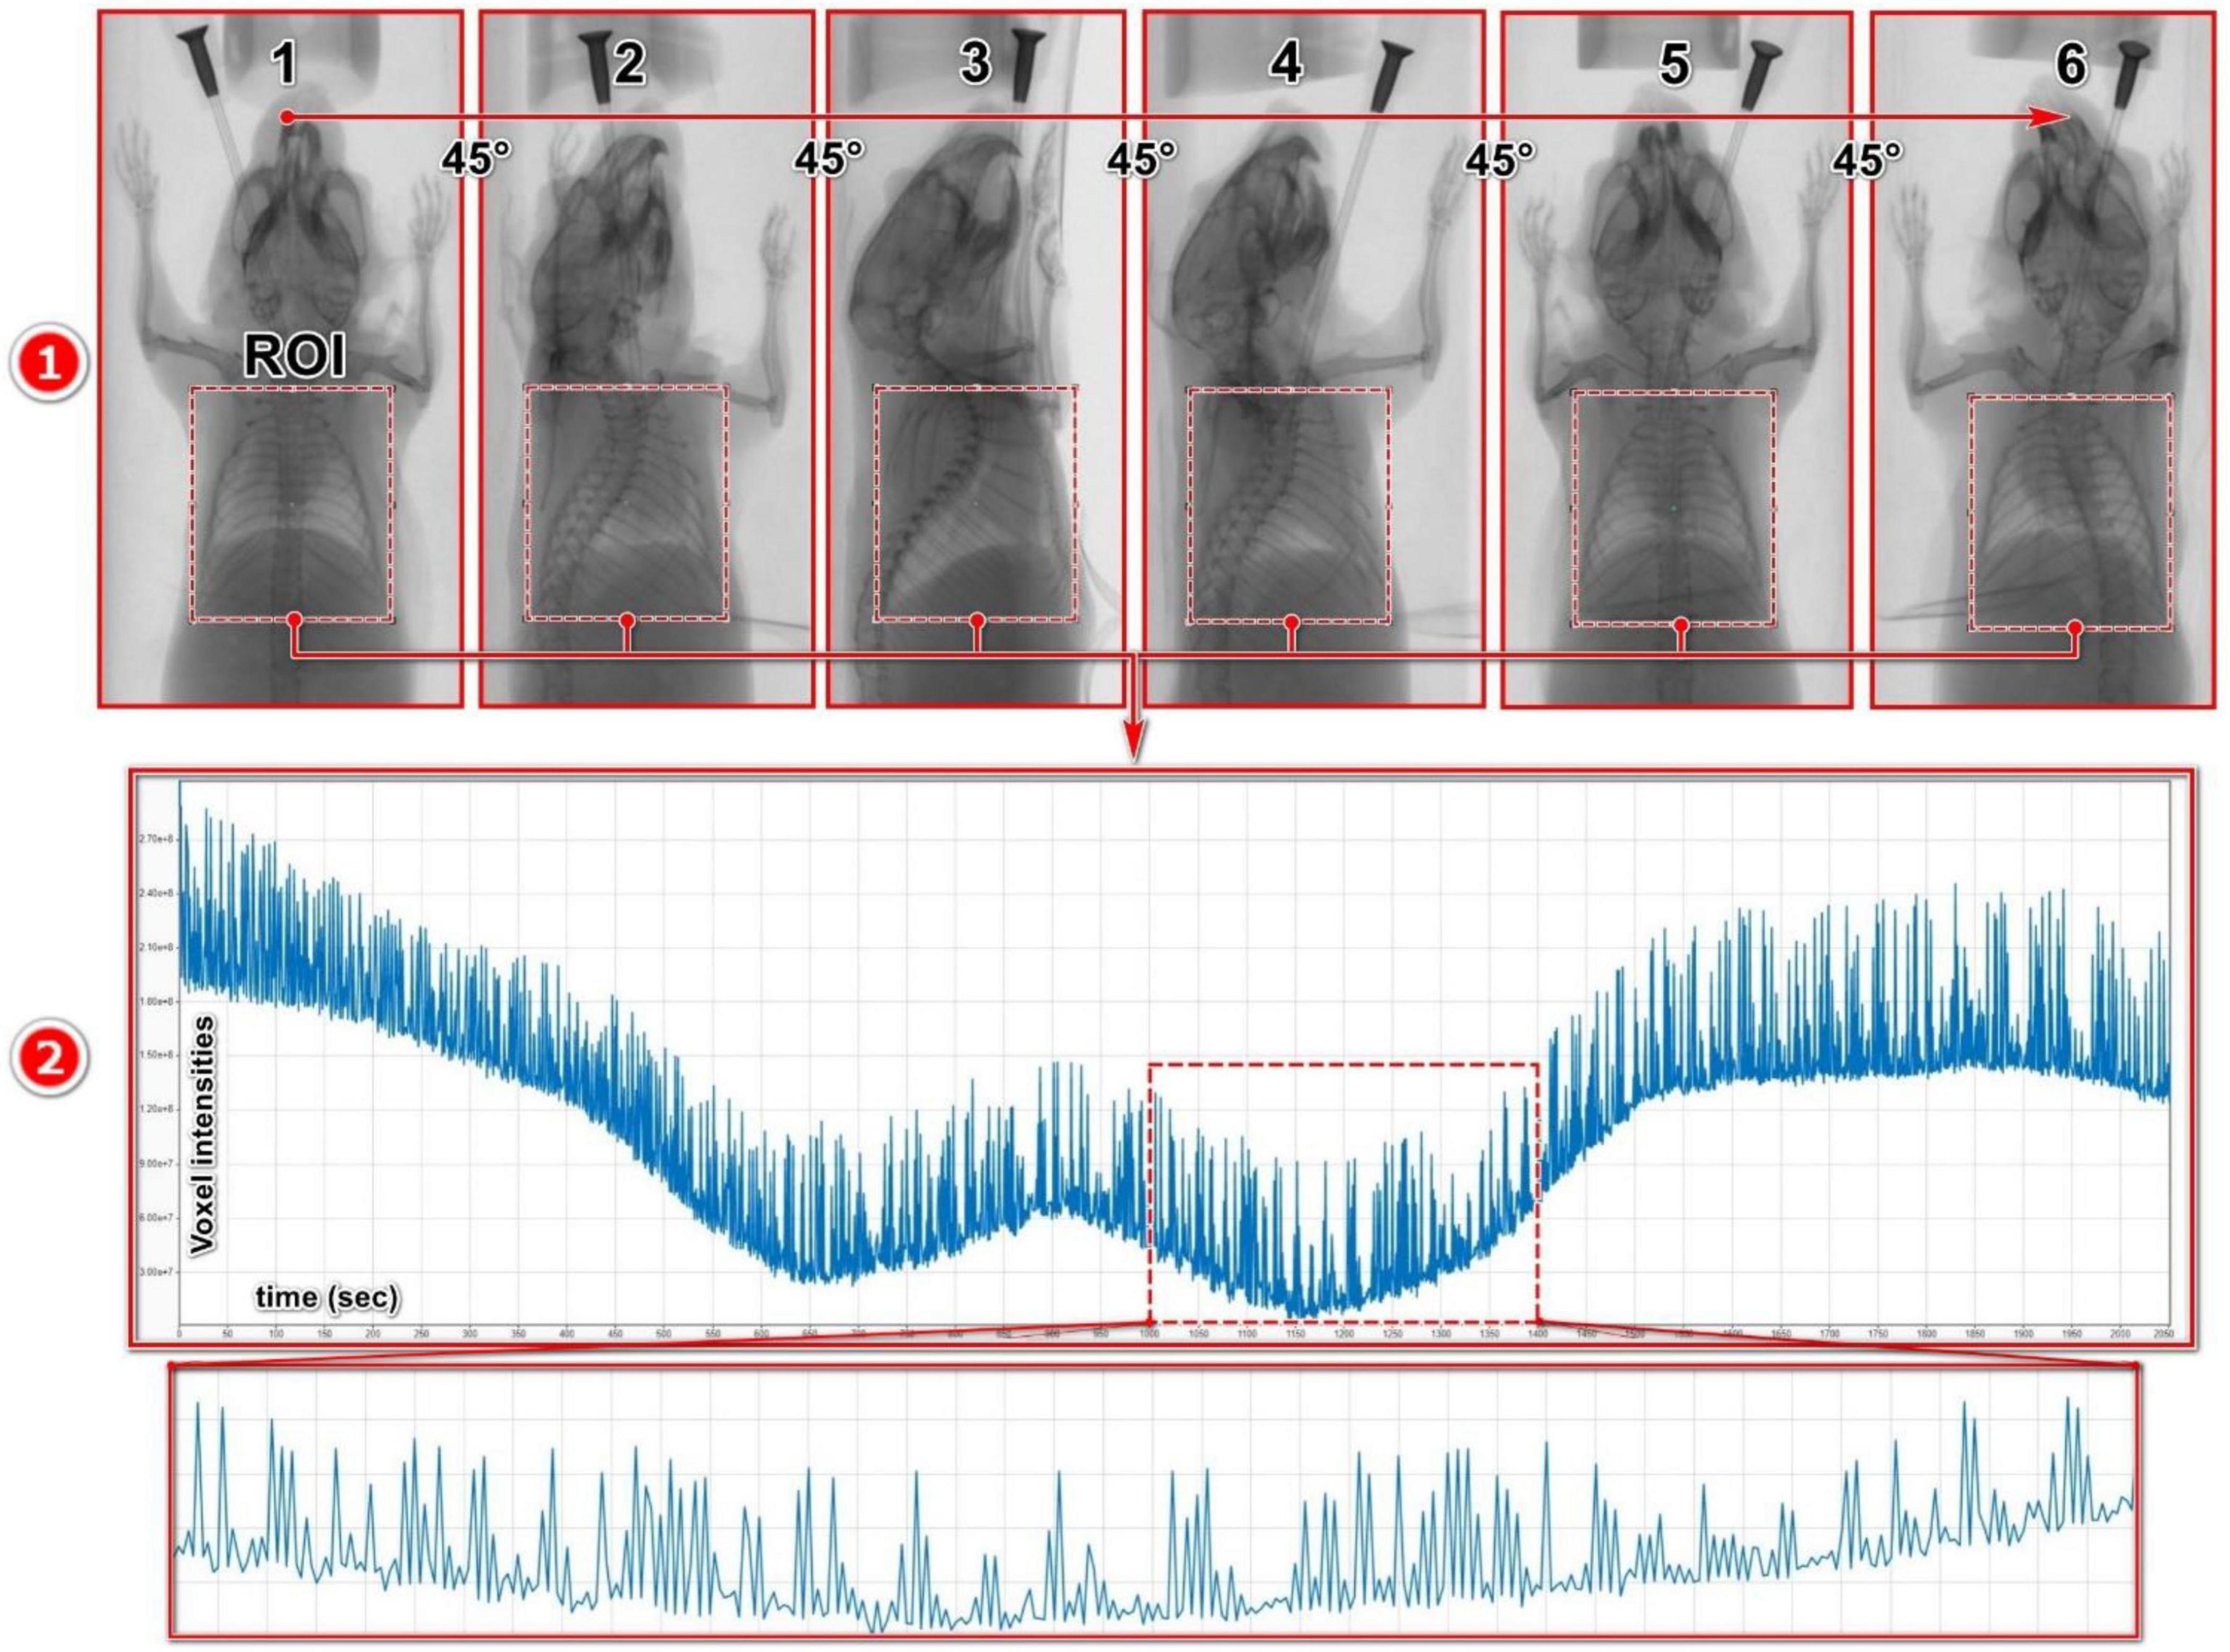

We obtained raw intensity curves based on the pixel intensity changes due to the diaphragm movements from the acquired 2D X-ray projection images. Thereto, the 2D X-ray projection images were imported into the DataViewer (version 1.5.6.2, Bruker) where several ROIs with benchmark angular positions separated by 45° rotation steps were manually placed on the lungs, encompassing the entire lung and diaphragm area (Figure 2.1). A simple rectangular-shaped ROI was used to cover the entire lung, as it was the fastest method to obtain a high-quality intensity curve.

Figure 2. Breathing signal acquisition from projection images: (1) Multiple ROIs with benchmark angular positions separated by 45° rotation steps were manually placed on the lungs, encompassing the entire lung and diaphragm. (2) The exported intensity curve, derived from the signal acquisition process, represents the average pixel intensity within the ROIs across all X-ray projections within the associated timeframe.

For the angular positions between the benchmark positions, the ROI positions are linearly interpolated from the benchmark ROIs to save time and streamline the process. To maintain consistency throughout the analysis, the size of the ROIs was kept identical across all the projections. The raw intensity curves obtained from the projection images represent amplitude curves that depict the average pixel intensity (attenuation) changes within the ROI for each projection of the dataset. These intensity curves consist of a combination of signals induced by various sources, including gantry rotation, respiratory and cardiac cycles, as well as noise (Figure 2.2).